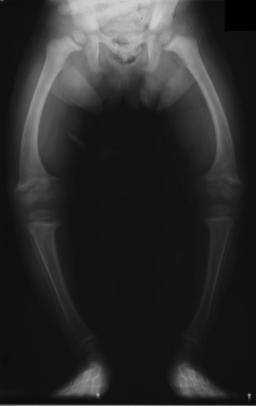

The only way to quantify adequate levels of vitamin D is with a serum 25(OH)D3 (calcifediol) test.[15] In the United States, serum 25(OH)D3 was below the recommended level for more than a third of white men in a 2005 study, with serum levels even lower in women and in most minorities. This indicates that vitamin D deficiency may be a common problem in the US.[16] Australia and New Zealand have had similar findings, which indicate insufficient protection against rickets for children and osteoporosis for adults.[17]